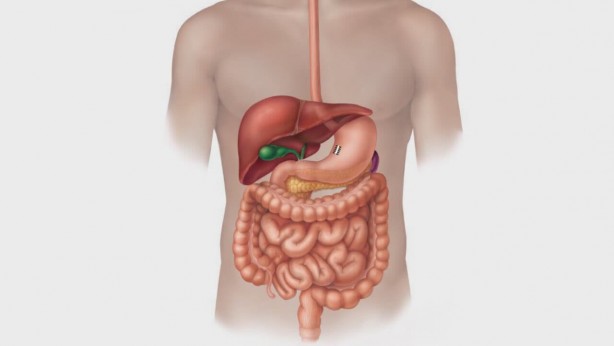

Kuru erik metabolizmayı hızlandırıyor, içerisindeki zengin lif oranı sayesinde kabızlığı önlüyor. Peki günde 6 adet kuru erik yerseniz ne olur? İşte kuru eriğin sağlık açısından şaşırtıcı faydaları... Kuru erik yapılan araştırmalara göre kilo verdiriyor. Kuru eriğin faydaları arasında kabızlığı önleme, metabolizmayı hızlandırma bulunuyor. Peki günde 6 adet kur erik yerseniz ne olur? İşte kuru eriğin sağlık açısından şaşırtıcı faydaları...